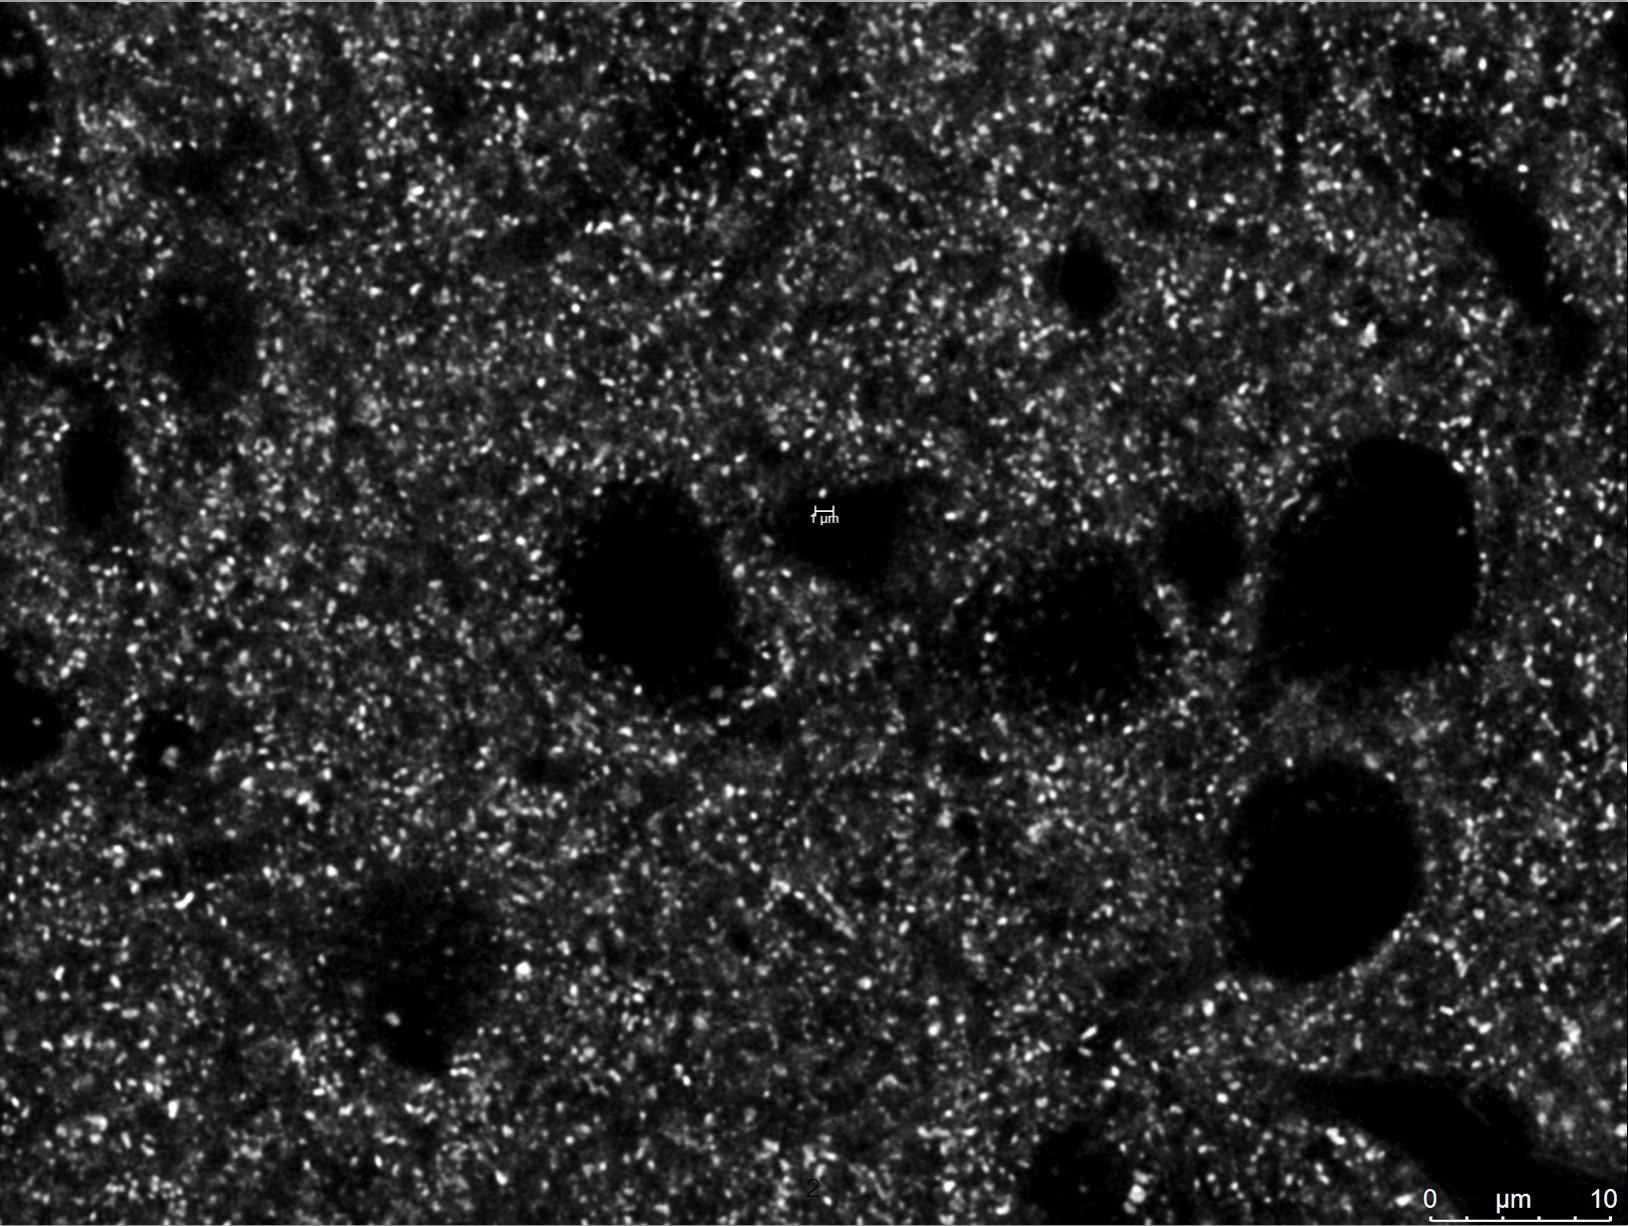

私たち生命は、化学分子の集合体でできています。生体に存在する分子の濃度・局在・相互作用・反応により、生命は成り立っています。しかし、個々の分子がどのように機能しているのか、その全容は未だ解明されていません。私たちのグループでは、「化学」の力で優れた機能を持つ「分子プローブ(生体探索/制御分子)」を創り出し、生命現象を分子レベルで理解・制御することを目指しています。分子を創る「有機化学」、化学で生命に迫る「化学生物学」、生命を知る「分析化学」の融合により優れた分子プローブを開発し、ヒトやマウスといった個体レベル(In vivo)での機能解析・制御法の開発に挑戦しています。

具体的には、生体内で重要な機能を発揮している特定タンパク質の機能解析、精神疾患・神経疾患などに関与が示唆される脳内の特定細胞の解析/機能化、がんの診断・治療につながる分子技術の開発などを多角的に取り組んでいます。これらの取り組みを通じ、未知の生体メカニズムの解明、そして分子情報を基軸とした革新的な医療診断・応用の実現を目指しています。